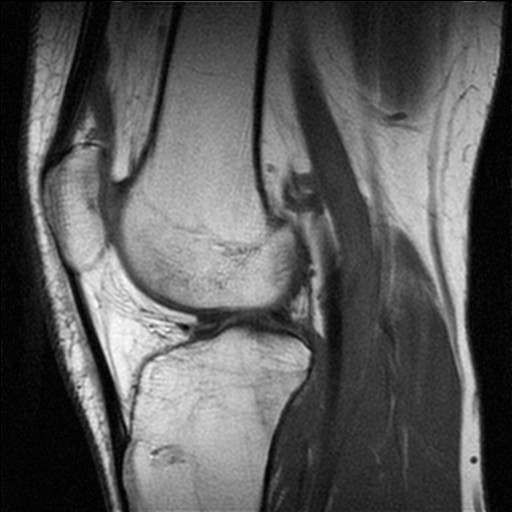

MRI scans in Sports Medicine – use or abuse?

In the article by Gina Kolata, a science journalist for the New York Times, Dr James Andrews, of the Andrews Institute for Orthopaedics and Sports Medicine, was quoted as saying ‘If you want an excuse to operate on a pitcher’s throwing shoulder, just get an MRI.’

The article claims that Dr Andrews was involved in a piece of research where the pitching shoulders of 31 asymptomatic Professional Baseball pitchers were scanned using MRI, with findings of ‘abnormal shoulder cartilage’ in 90% of the shoulders, and ‘abnormal rotator cuff tendons’ in 87% of the shoulders. There was no indication as to whether or not this research was published.

Other clinicians are subsequently quoted, including Professor Bruce Sangeorzan, Vice Chairman of the Department of Orthopaedics and Sports Medicine at the University of Washington saying ‘an MRI is unlike any other imaging tool we use… It is a very sensitive tool, but it is not very specific. That’s the problem.’

In addition, Professor Christopher DiGiovanni, Sports Medicine and Orthopaedic Specialist at Brown University, is quoted as saying ‘It is very rare for an MRI to come back with the words “normal study” … I can’t tell you the last time I’ve seen it.’

They would also surely realise issues regarding the sensitivity and specificity of MRI scans for detecting lesions, and the fact that the natural history of some lesions detected by MRI scans that have hitherto been undetectable is not well known, limiting the conclusions that can be drawn from some scans relating to treatment and prognosis.